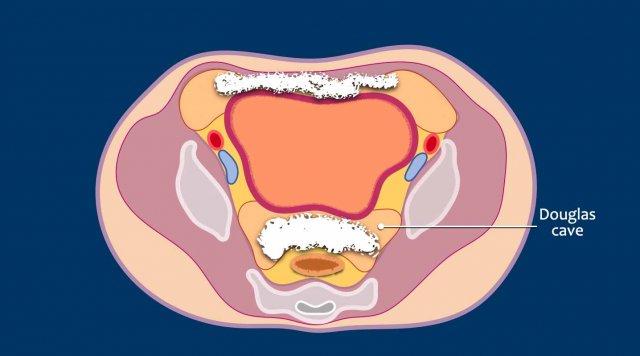

Ở vùng chậu, vị trí quan trọng nhất là túi cùng trực tràng-tử cung và trực tràng-bàng quang (túi cùng Douglas).

Đôi khi có thể thấy di căn khối u lan ra phía trước bàng quang, nhưng không xâm lấn thành bàng quang, do bàng quang là cơ quan nằm ngoài phúc mạc.

Tuy nhiên, vòm bàng quang phía trên và ống niệu rốn được ngăn cách với khoang bụng bởi một lớp phúc mạc thành, tạo thành đích tiềm năng cho các tế bào khối u.

Đặc biệt khi bàng quang đầy, các tổn thương di căn phúc mạc có thể được quan sát thấy ở phía trước bàng quang, áp sát thành bụng trước.

Đây không phải là bệnh lý quanh bàng quang, vì khoang quanh bàng quang nằm ngoài phúc mạc và không thông với khoang trong phúc mạc.